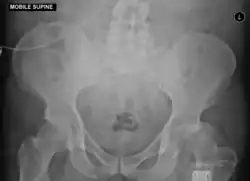

Anterior-posterior (AP) X-rays of the pelvis, AP and lateral views of the femur (knee included) are ordered for diagnosis.[13] The size of the head of the femur is then compared across both sides of the pelvis. The affected femoral head will appear larger if the dislocation is anterior, and smaller if posterior.[14] A CT scan may also be ordered to clarify the fracture pattern.